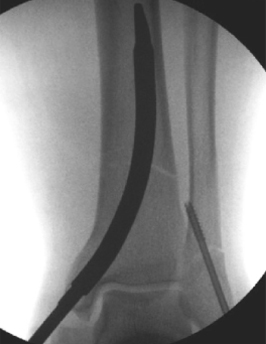

Figuri 3 u 4:

Immaġini radjografiċi u ta 'rkupru wara l-operazzjoni

Inċiżjoni lonġitudinali ta '2-3 ċm issir fil-ponta tal-malleolus medjali biex tesponi l-ligament tad-deltojde superfiċjali. Pin ta 'gwida hija mdaħħla fil-ponta tal-malleolus jew kemmxejn medjali (Fig. 2a), 4-5 mm mill-wiċċ tal-artiku. Veduta laterali turi inserzjoni permezz tal-kanal interkondilari (Fig. 2b), tevita ħsara lill-muskolu tibialis posterjuri. Issepara l-ligament tad-deltojde superfiċjali, imbagħad uża reamer biex tkabbar il-kanal medullari sal-reġjun metafisjali (Fig. 2c). Neħħi l-għadam kanċellat ħdejn il-kortiċi medjali prossimali biex daħħal id-dwiefer (Fig. 2d). Daħħal dwiefer ta 'prova biex tikkonferma d-daqs DTN (Fig. 2e). Evita t-tiswir jew il-brim eċċessiv biex tevita ksur malleolari medjali jatroġeniku. Aġġusta l-fond tad-dwiefer biex tiżgura li l-viti distali ma jidħlux fil-ġog tal-għaksa jew fis-sit tal-ksur. L-iffissar jinkiseb b'viti li jillokkjaw f'xulxin u distalment.

Għandha tingħata attenzjoni biex tiġi evitata l-penetrazzjoni tal-kamin fil-talja tal-fibular. L-apparat ta 'pożizzjonament jista' jikkawża rotazzjoni posterjuri tad-DTN minħabba l-piż tiegħu; aġġusta t-tieni kamin biex tipponta lejn il-fibula (Fig. 4c).Kumplikazzjonijiet potenzjali: